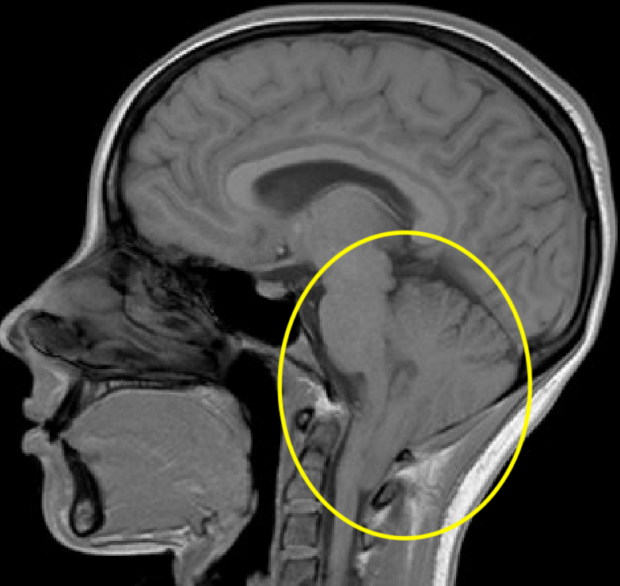

Hi there, does this look like Chiari at all? It's supine, not upright What Does Chiari Neck Pain Feel Like my neck pain is pretty intense. You may also have a pocket of spinal fluid in the spinal cord or brain stem. The types and severity of. chiari malformations (cm) are caused by problems in the structure of the brain and skull. what does a chiari malformation feel like? chiari & comorbid symptoms compilation. if. What Does Chiari Neck Pain Feel Like.